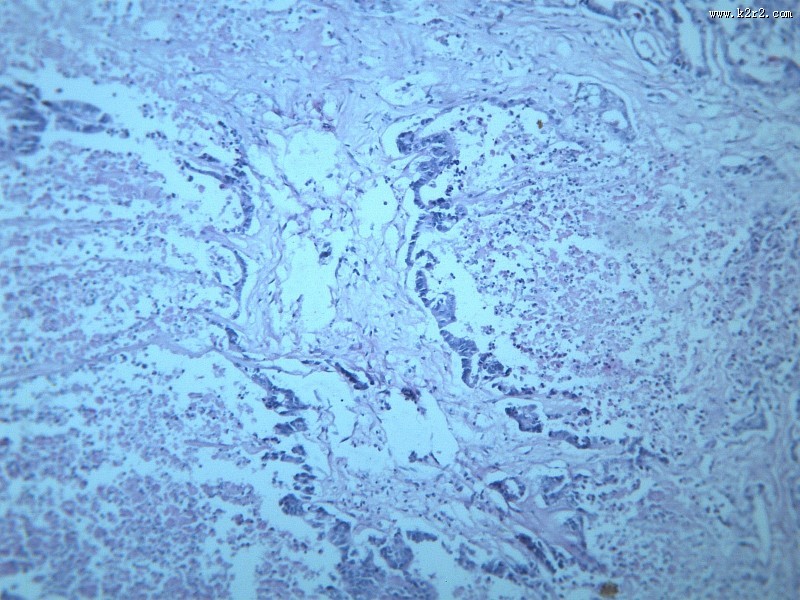

腺癌肝转移大全 - 第8张

第 8 / 12 张

腺癌肝转移大全

图集中 / 共有 12 张图片

腺癌

腺癌肝转移